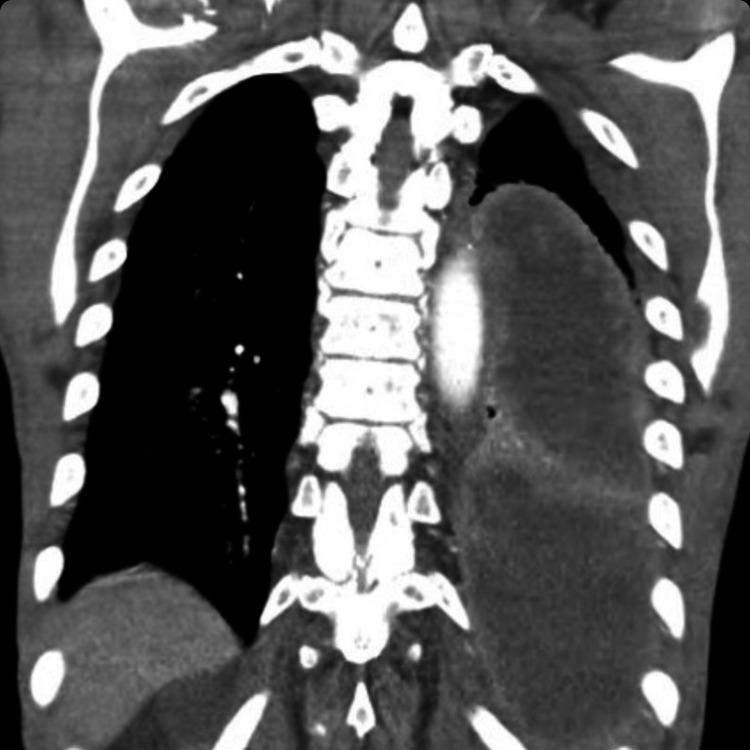

Right-sided native valve infective endocarditis (IE) refers to IE involving the tricuspid or pulmonic valve. The most common factors causing right-sided IE include intravenous drug use, intracardiac device, and central venous catheters. Isolated pulmonic valve IE has only been reported in less than 2% of all IE cases. We present a unique case of a patient with a history of poor oral hygiene found to have isolated blood culture-negative pulmonic valve IE, who subsequently developed empyema positive for .

右侧自体瓣膜感染性心内膜炎(IE)是指累及三尖瓣或肺动脉瓣的IE。导致右侧IE的最常见因素包括静脉药物使用、心内装置和中心静脉导管。孤立性肺动脉瓣IE在所有IE病例中报告的比例不到2%。我们报告了一例独特病例,该患者有口腔卫生不良史,被发现患有孤立性血培养阴性的肺动脉瓣IE,随后并发了阳性的脓胸。